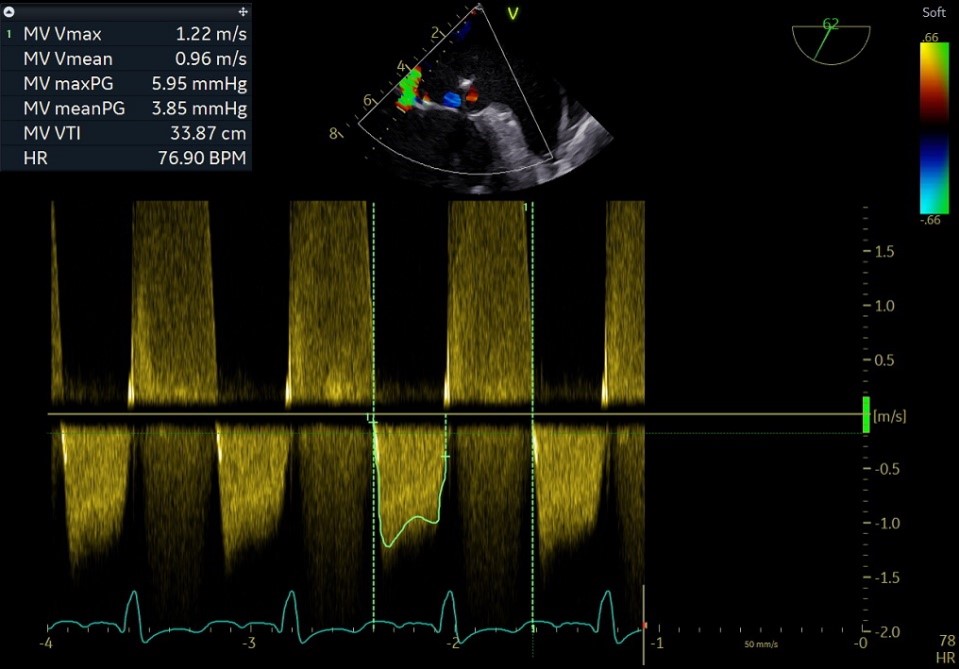

释放后

外侧2偏1区可见后叶栓系,下方空间乳头肌腱索杂多,后叶长度也一般,跨瓣压差3mmHg,第三枚夹子选择了NT,打算靠近第一枚夹子2偏1区夹持,置入NT后,在1区上方做轨迹测试,充分释放张力,调整夹子的夹臂方向位于1点-7点的方向,回拉系统,使第三枚夹子靠近第一枚夹子,关小夹子进入到心室侧,由于第一枚夹子起到了稳定瓣叶的作用,第三枚夹子捕捞夹持相对顺利,一次精准捕获前叶和后叶,再次完整评估二尖瓣NT的方向、组织桥稳定性、瓣叶受限程度及反流减小程度。反流改善到1+-2+,平均跨瓣压差3.85mmHg,左房压明显下降,肺静脉逆流明显改善,手术完美结束。

术后肺静脉频谱

术后平均跨瓣压差